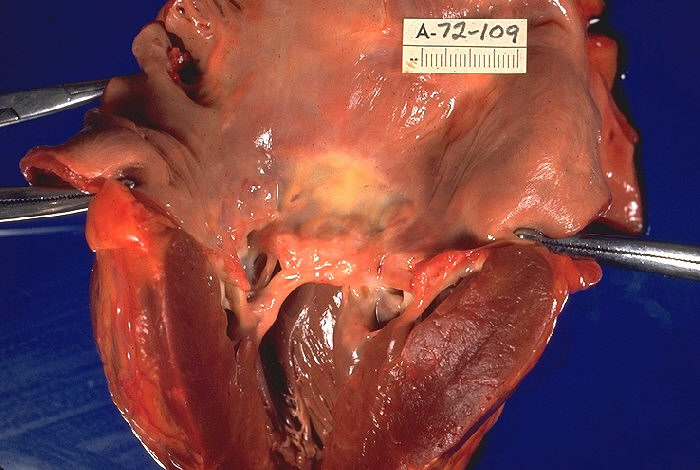

심장 초음파 검사를 이용하여 승모판 협착을 진단한다.[4] 심장 초음파 검사는 좌심방 비대, 좁고 "물고기 입" 모양의 개구부를 가진 두껍고 석회화된 승모판, 그리고 진행된 질환의 우심실 부전 징후를 보여준다.[4] 또한, 승모판 엽의 개방 감소와 확장기 동안 증가된 혈류 속도를 보여줄 수 있다. 도플러 심장 초음파 검사로 측정된 경승모판 압력 차는 승모판 협착증의 중증도를 평가하는 골드 스탠다드이다.